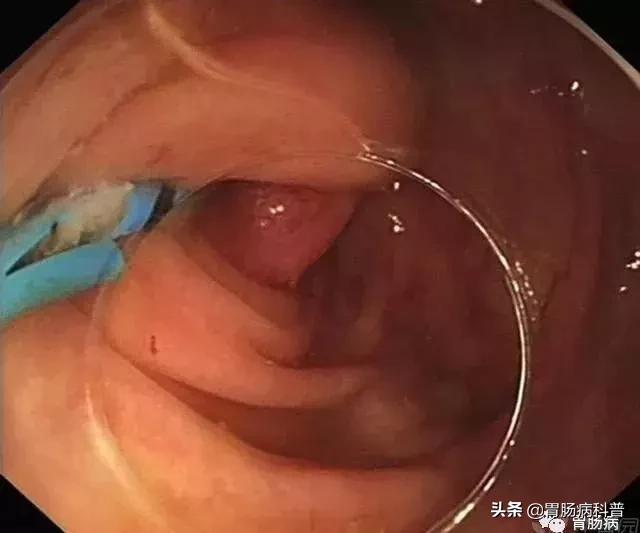

正常的阑尾开口部都被Gerlach’s瓣覆盖(如图,双箭头示Gerlach’s瓣);

通过内镜前端的透明帽的帮助下,推开Gerlach’s瓣(黄箭头),并进行阑尾腔插管。

3.球囊或网篮取石术:

通过内镜下置入球囊导管或取石网篮,将粪石取出,原理如ERCP取石术。(黑箭头示取出的粪石)。